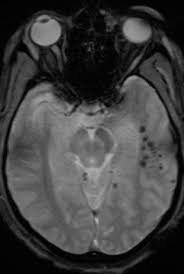

Ct Head Scan Familydoctor Org

Ct Head Scan Familydoctor Org from familydoctor.org